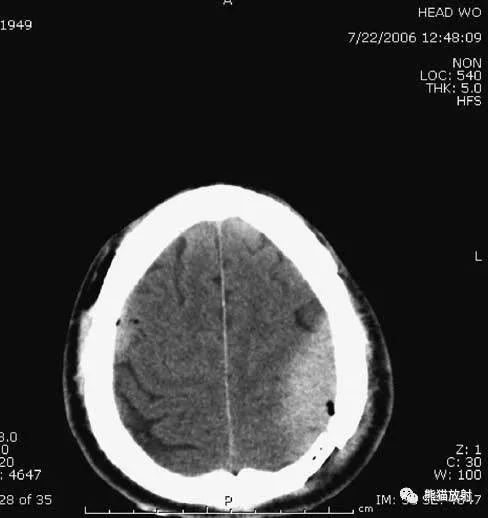

5、高血压性脑出血

高血压性脑出血:自发性出血;

继发于长期高血压及慢性血管病;

常见于基底节区、丘脑、脑桥、小脑。

A:占位效应,相邻脑沟、脑池消失;

F:脑出血破入四脑室。

▲钩回疝:

是当代偿机制不能适应占位性病变时的结果。

基底节区大量高血压性脑出血,破入脑室及蛛网膜下腔,周围水肿,脑干周围空间消失;脑干出血、脑积水。